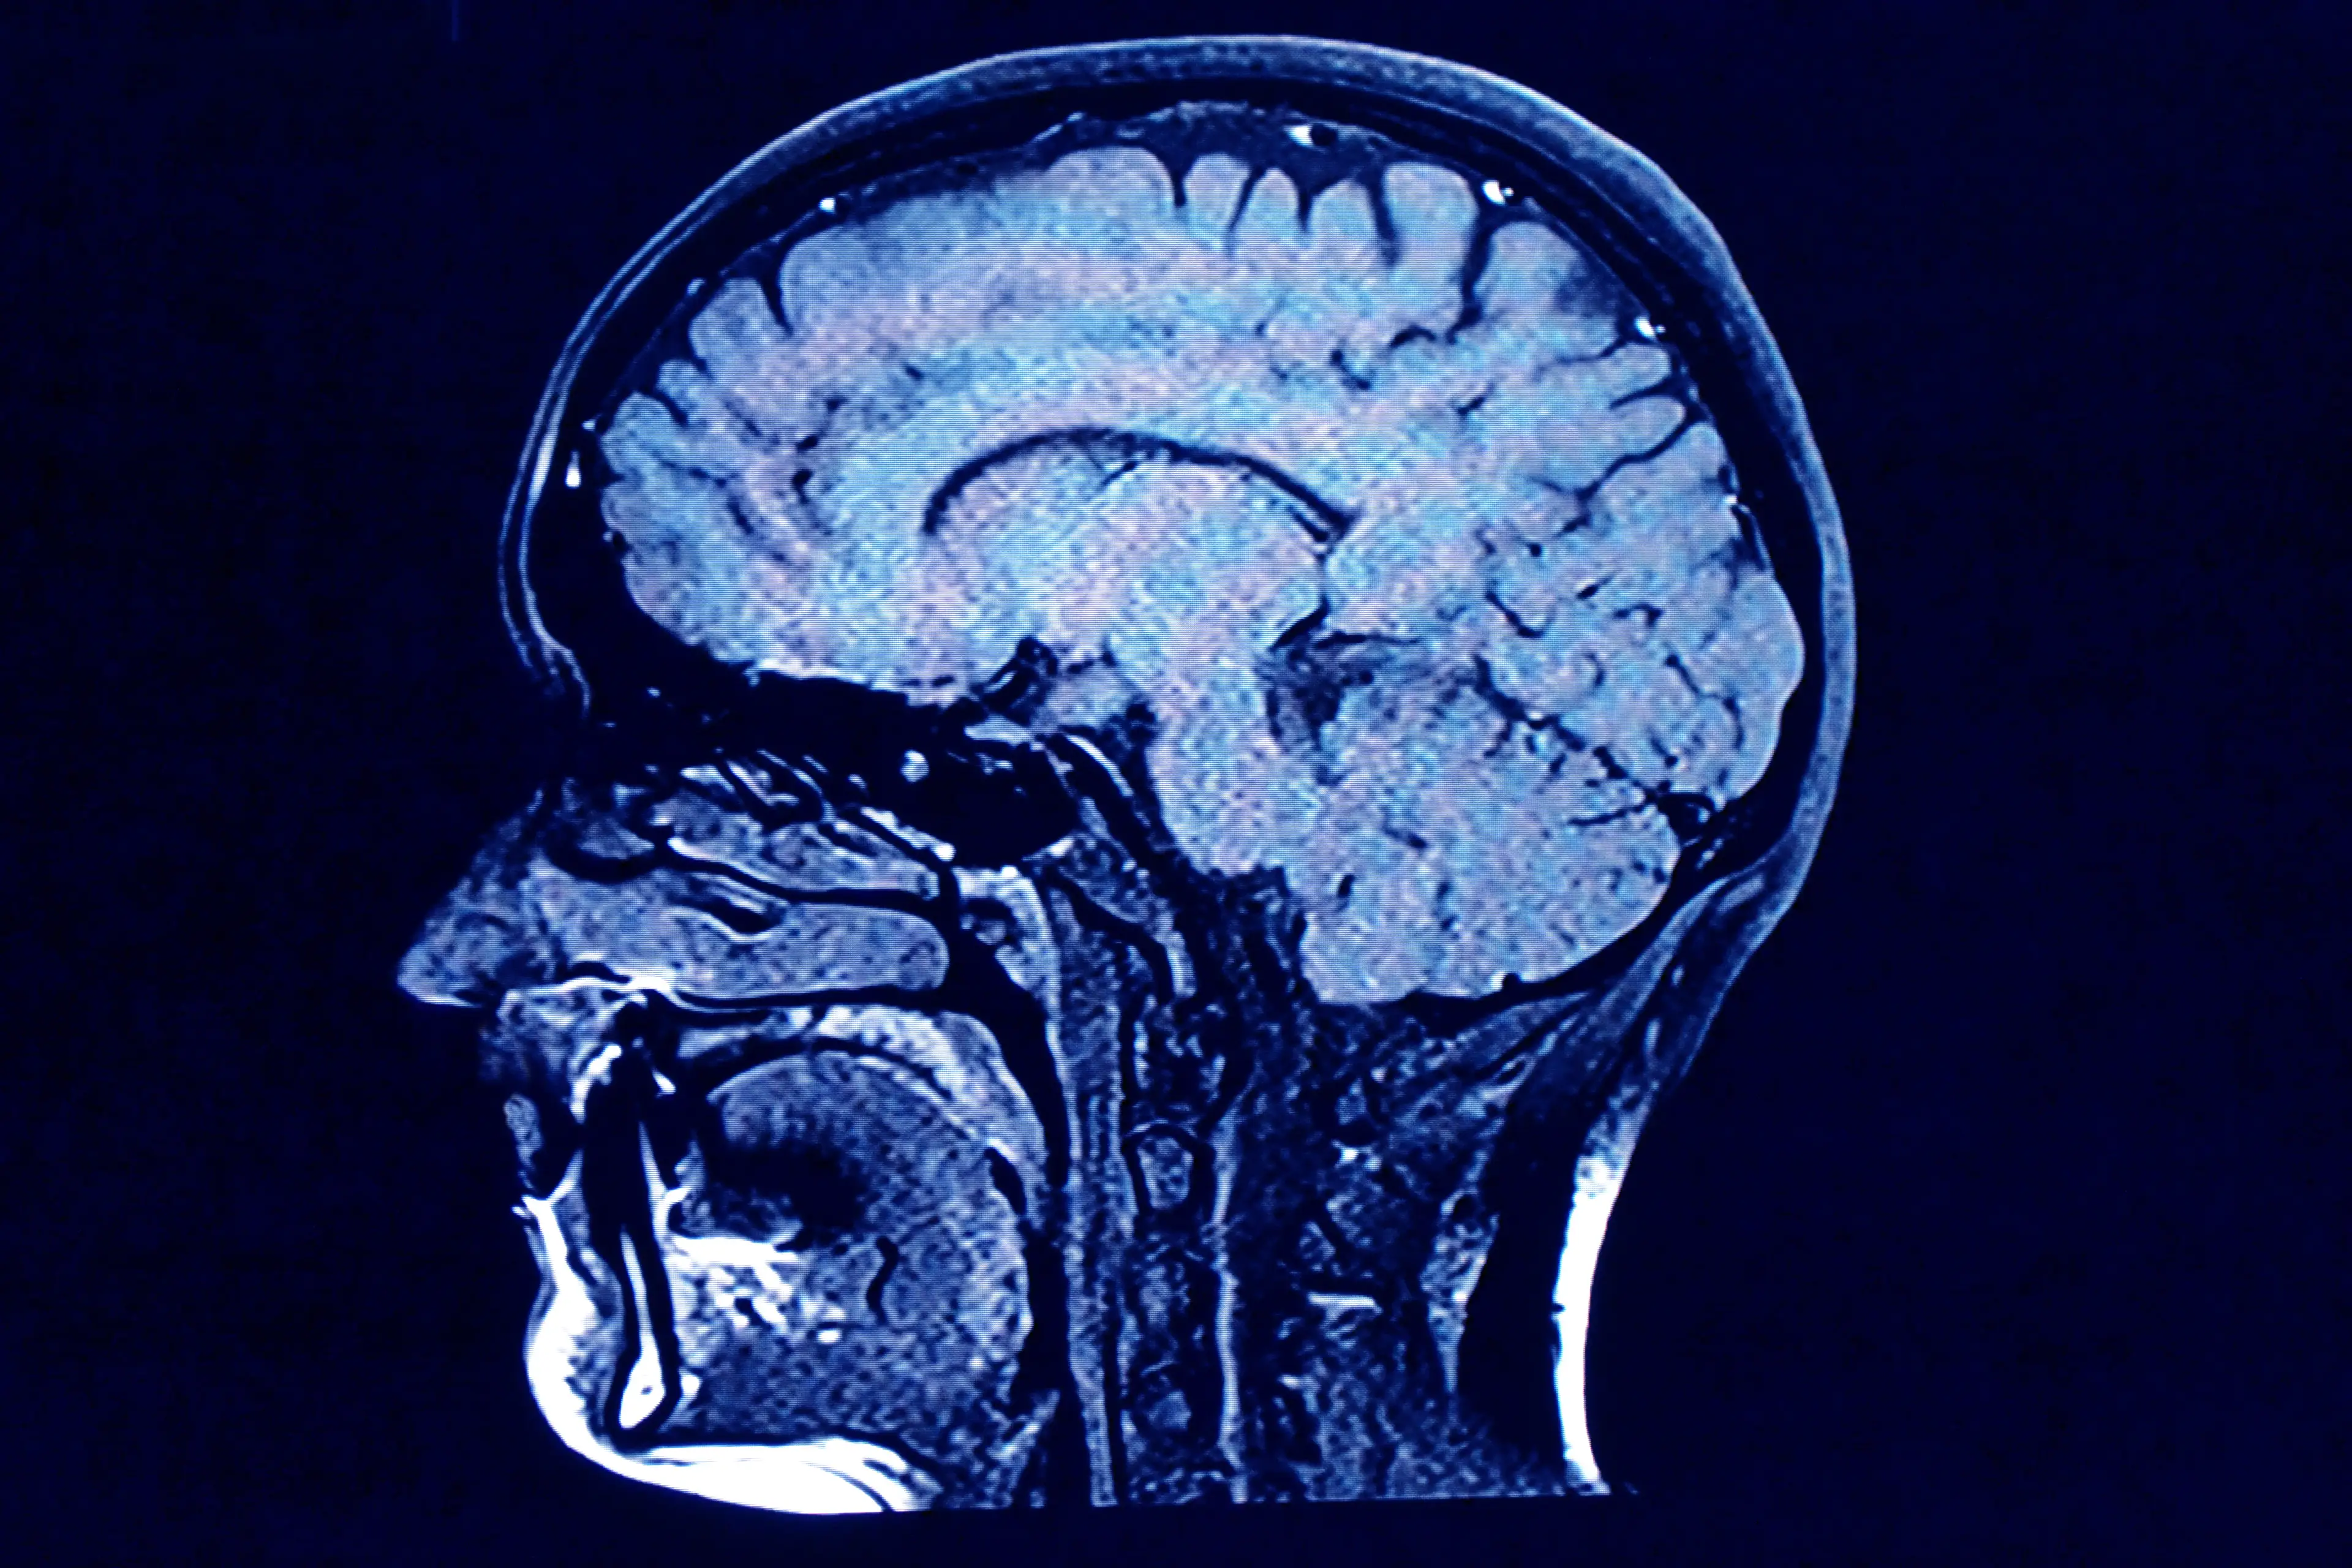

According to researchers, it could help to shed more light on how our brains work and could even be used to treat neurological disorders.

The new tech will help to give us a better understanding of some of the brain functions, including emotion, social behavior and cognition.

According to IBS, the human contains over 100 billion neurons interconnected in a complex network and the device will be able to control the neural circuits that are crucial for understanding higher brain functions as well as identifying the causes of various brain disorders.